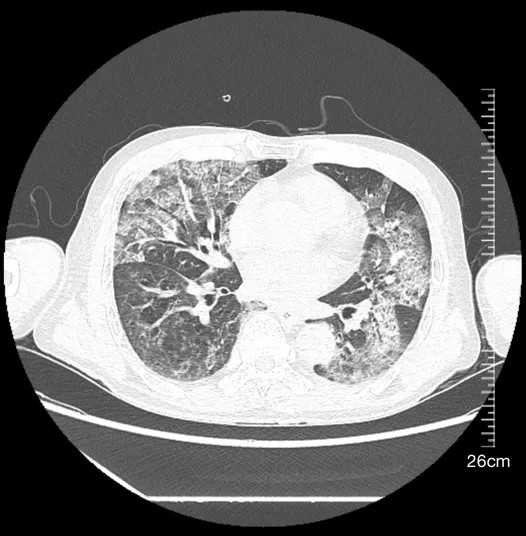

第三阶段(2024年7月-2025年5月):转诊专科医院康复治疗后仍遗留舌体偏斜、饮水呛咳,多次肺部CT显示游走性炎症病灶,肺功能显著受损(DLCO 50-60%),激素减量困难,血压血糖控制不佳,治疗陷入僵局。

2025年5月27日肺部CT平扫影像

1.影像追踪:影像科刘烽副主任医师、呼吸与危重症医学科林劲榕主任医师指出,对比患者既往多次CT、肺泡灌洗检查、抗生素及激素治疗结果发现,肺部病灶、病原学检查结果、激素治疗反应与误吸特征高度吻合,且出院后多次肺部CT结果提示“游走性炎症”提示反复微量误吸;结合颅脑MRI及吞咽障碍病史,确认急性延髓梗死导致咽喉肌群功能障碍,为误吸根源;